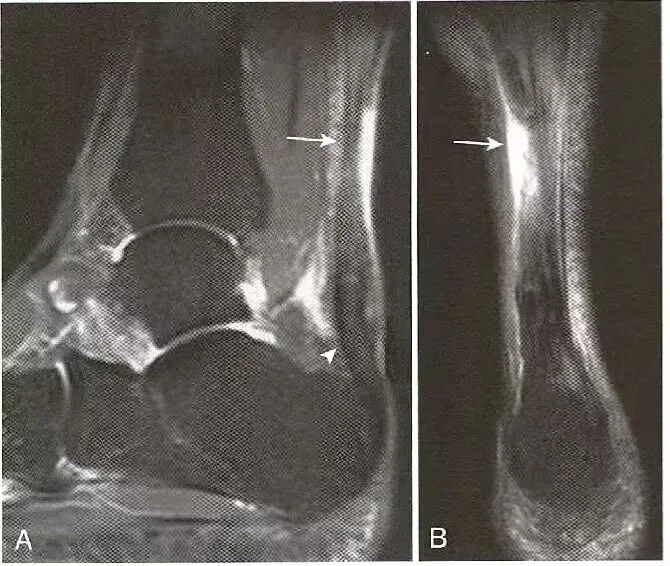

部分肌腱撕裂:  A,跟腱远端明显增厚,近端重度部分撕裂的部位明显变薄;B,脂肪抑制序列显示了肌腱断裂的程度。